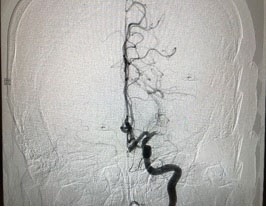

Từ kết quả khám lâm sàng và các xét nghiệm chẩn đoán hình ảnh hiện đại (CT/MRI/MRA), chị Hoa được chẩn đoán nhồi máu não tối cấp do tắc hoàn toàn động mạch não giữa trái. Đây là bệnh tiên lượng nặng, nguy cơ tử vong và tàn phế cao.

Các chuyên gia hàng đầu về đột quỵ tại khu vực miền Trung gồm BS Nguyễn Thái Trí - Trưởng khoa cấp cứu và TS.BS Tôn Thất Trí Dũng - Trưởng khoa Khám bệnh - Nội khoa, Bệnh viện Vinmec Đà Nẵng nhận định, cần thực hiện ngay các biện pháp tái thông mạch máu tái tưới máu não. Không để lãng phí phút giây nào, các bác sĩ đồng thời thực hiện 2 kỹ thuật cấp cứu là làm tan cục máu đông bằng thuốc và can thiệp lấy huyết khối qua đường động mạch.

Hình ảnh chụp mạch máu của chị Hoa bị tắc trước và sau khi được các bác sĩ Vinmec Đà Nẵng can thiệp. |

Kết quả, mạch máu của người bệnh được thông lại sau 40 phút nhập viện và dưới 6 giờ từ khi đột quỵ. Sau can thiệp, tình trạng của bệnh nhân cải thiện rõ rệt. Chị Hoa cử động tốt chân tay bên phải, tỉnh táo, nói và trả lời chính xác tuy chưa được tròn chữ.